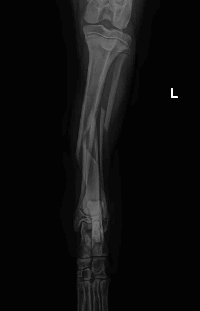

Após exames recebemos a seguinte notícia:

Em relação às fraturas, além da perninha esquerda, ela tem também fraturas em pelve. O ortopedista nos repassou o orçamento de R$2950,00 para o procedimento cirúrgico (incluindo o valor da anestesia e uma diária de pós operatório). Na ultrassonografia abdominal, foi identificado apenas sinais de gastrite. Os exames de sangue devem ser liberados agora pela manhã ainda.